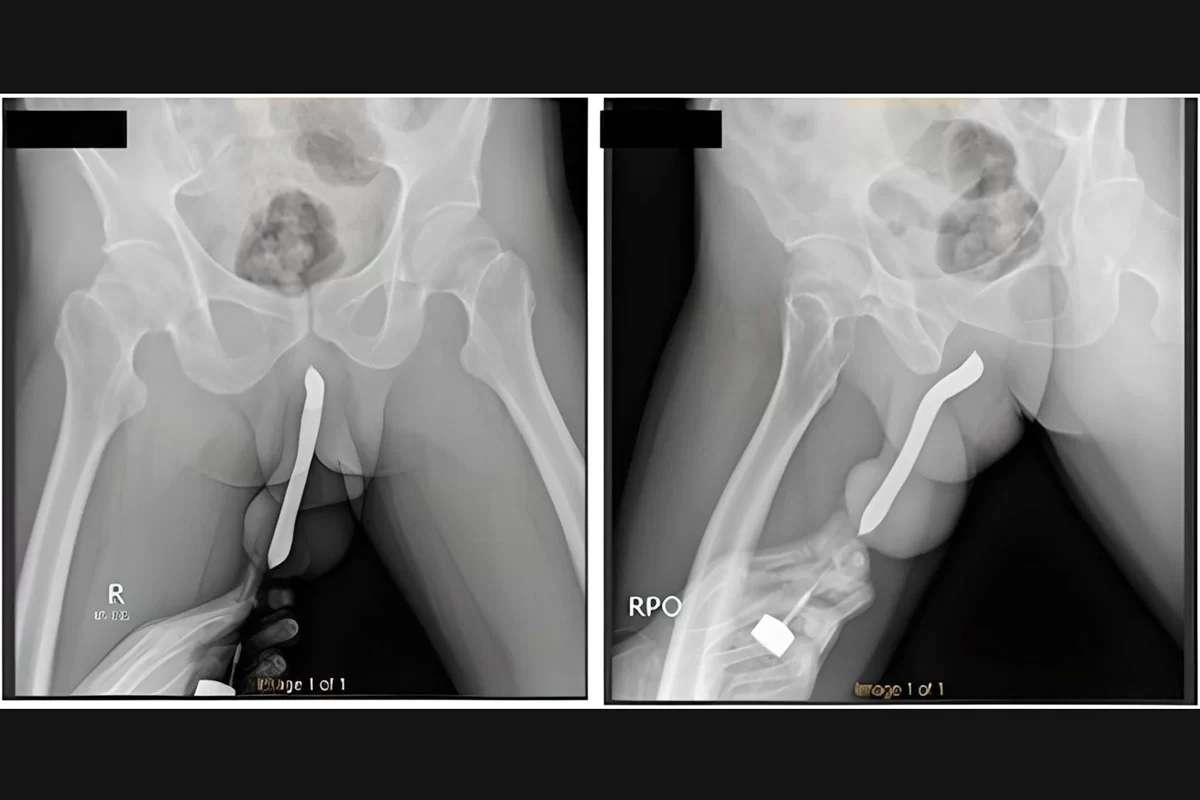

O homem ainda esperou cerca de 12 horas após o acidente para procurar ajuda médica. Os profissionais do Hospital Geral Acadêmico Soetomo, na cidade de Surabaya, descrevem que a situação do pênis era complicada. O órgão estava, além de inchado, muito deformado por conta da escova que ainda estava dentro.

O homem admitiu aos socorristas do hospital que colocou a escova por “satisfação pessoal”. Ele já havia adiantado que fez um pequeno corte no órgão. Ele teria como finalidade facilitar a introdução de mais objetos no órgão. A “anomalia” foi feita em 2017, entretanto não foi informado se a escova estava dentro desde então.

O indonésio precisou passar por uma cirurgia de duas horas para retirada da escova. Ele recebeu alta 3 dias depois e não sofreu complicações, conseguindo urinar normalmente. Embora não tenha ossos, o pênis tem tubos esponjosos que enchem de sangue, deixando ele ereto. As fraturas são super comuns nesta região.